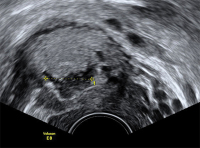

Tipps und Tricks im Gyn-Ultraschall: Die Sectionarbe am nichtschwangeren Uterus und in der Frühschwangerschaft

Journal für Gynäkologische Endokrinologie 2014; 8 (2) (Ausgabe für Österreich): 22-24 Journal für Gynäkologische Endokrinologie 2014; 8 (2) (Ausgabe für Schweiz): 24-26 Volltext (PDF) Abbildungen